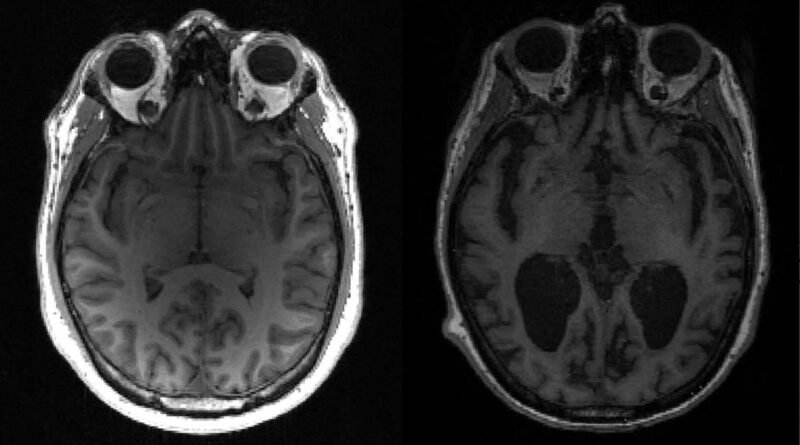

A empresa está desenvolvendo um imunizante para o Alzheimer que visa combater os oligômeros beta-amiloide — que são cadeias de proteínas que quando se acumulam no cérebro provocam as manifestações clínicas da doença. O imunizante estimula a produção de anticorpos que podem reconhecer as formas beta-amiloide capazes de desenvolver neurotoxinas.